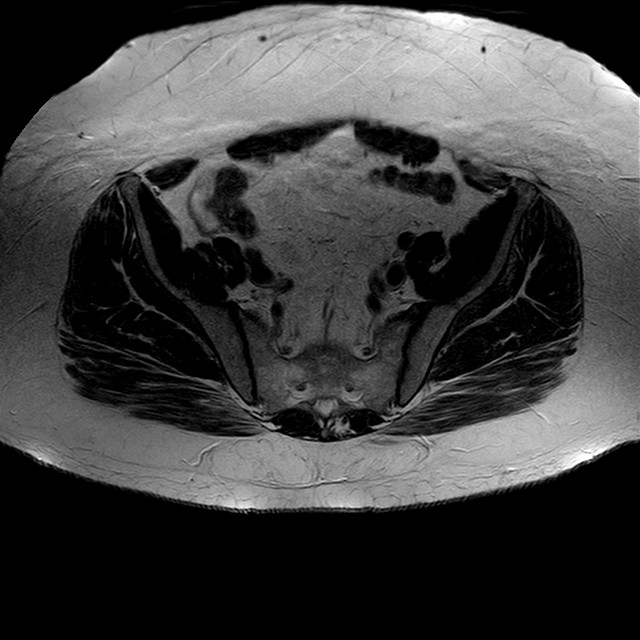

Esami: RMN BACINO

eT2w TSE

Evidenti e simmetriche alterazioni osteofitosiche in regione coxo femorale con riduzione delle rime articolari. Degenerazione completa del cercine glenoideo. Non attuali segni di versamento articolare. Non segni di edema osseo che escludono attuale algodistrofia od osteonecrosi. Lieve e simmetrica riduzione del trofismo della muscolatura glutea.